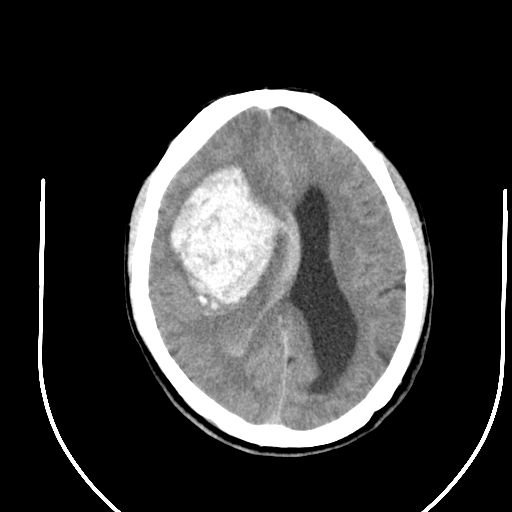

标题: CT24997:M,60Y,突发昏迷30分钟,有高血压病史。 [打印本页]

标题: CT24997:M,60Y,突发昏迷30分钟,有高血压病史。

右侧基底节区脑出血并破溃入脑室。

支持楼主诊断,脑中线结构有偏移,脑疝形成可能!

1右侧基底节脑出血伴脑干出血并破入脑室系统脑疝形成2梗阻性脑积水

1)右侧基底节脑出血伴脑干出血并破入脑室系统。2)大脑镰下疝。3)梗阻性脑积水。

1、右侧基底节脑出血伴脑干出血并破入脑室系统。

2、大脑镰下疝。

3、梗阻性脑积水。